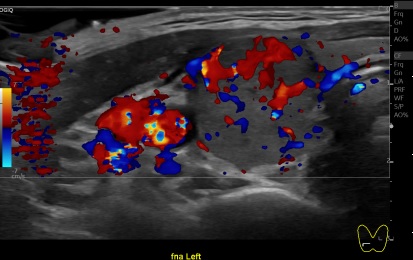

상기환자 외부검사이상소견 정밀검사위해 내원하신 40대초반 여성분으로 갑상선 초음파 시행후 의심스러운 갑상선 좌엽 결절 세포검사 진행후 갑상선암으로 진단되었습니다